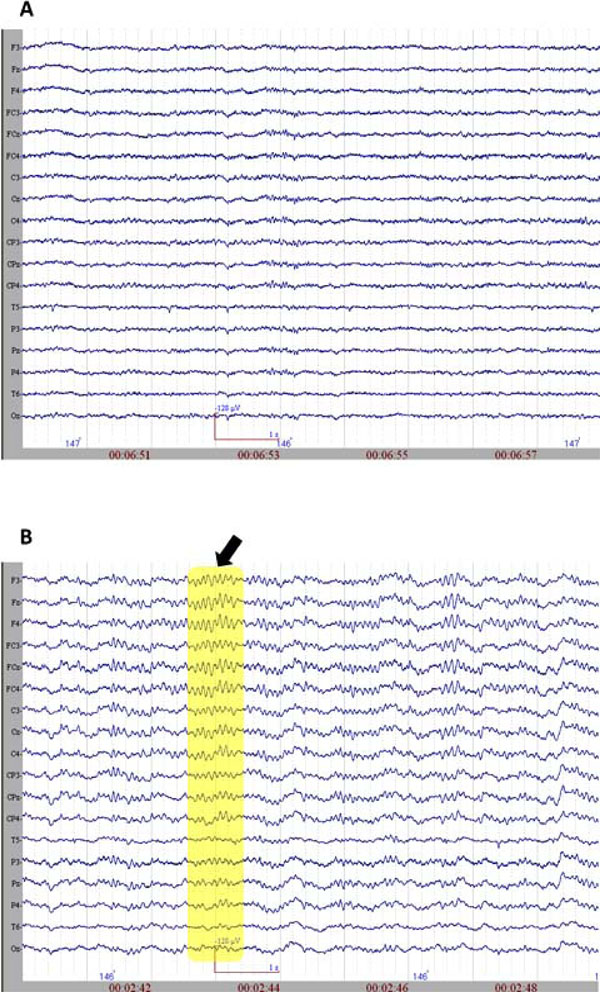

Global Spectral Changes in the EEG During Propofol Administration

The initiation of propofol resulted in the decrease of spectral variability in the continuous EEG. Fig. (2) displays raw EEG sections with two levels of anesthesia from the non-medicated and medicated conditions. The variability further decreased when reaching to 0.8 µg/mL level, where finally almost all the activity was composed of mono-frequency spectrum 13.20 (±2.56) Hz. These spindle oscillations dominated the EEG recording during the majority of the propofol 1.6 µg/mL levels. These oscillations lasted about 1001.04 (±221.02) milliseconds and had a range of 57.93 (±17.69) µV of amplitude. The spectral plot of a selected EEG segment with a spindle is provided in Fig. (3). As can be observed from the spectrogram, the EEG activity is locked into a narrowband of oscillatory activity of 13 Hz.

A. The raw EEG section (sample) from non-medicated group. B. The raw EEG section (sample) from medicated group. The arrow and the rectangular selection point to spindle oscillations.